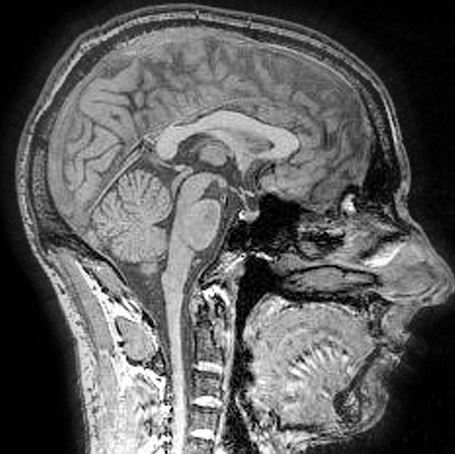

First, what is conversion disorder? Imagine an employee suffers a compensable injury to his right shoulder. He undergoes surgery, after which he contends he is completely unable to move his right arm. His physicians run numerous tests, none of which reveal any evidence of an etiology that explains the employee’s inability to move his arm. He may be intentionally refusing to move his arm, or he may be suffering from an underlying psychological condition that prevents him from doing so. Different from malingering, (in which a patient intentionally presents exaggerated symptoms), and factitious disorder, (in which the patient’s motor-sensory deficits are under voluntary control to play the role of an injured person), conversion disorder is an involuntary underlying psychological condition which results in blindness, paralysis, or some other neurological symptom that cannot be explained by medical evaluation.